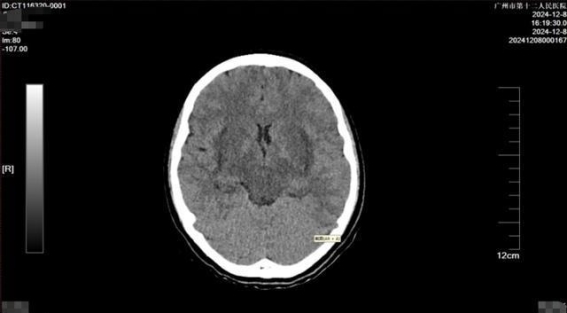

转运过程中,小美的生命体征几乎无法测量,心率急剧飙升至189次/分钟,血压已经无法测定,血氧饱和度也处于极低水平。广州医院在接诊的第一时间,启动了绿色通道,迅速为她进行了全面检查。经过紧急评估后,医生们决定实施个性化的治疗方案,包括精细化液体管理、血液净化、肺保护及脑保护措施等。整个过程极其紧张,医生们争分夺秒,为小美的生命展开了一场生死较量。

经过了2小时的紧急治疗后,小美的生命体征逐渐恢复稳定,血压和心率逐步上升。病情依旧严峻。小美的全身仍然出现了凝血功能异常,多个器官功能衰竭,中毒性脑病的症状十分明显。她全身各部位出现了渗血,特别是口腔、咽喉及气道内出血明显,这使得气管插管等医疗操作变得极其困难。但即便如此,重症医学科的团队始终没有放弃,对她实施全方位治疗。